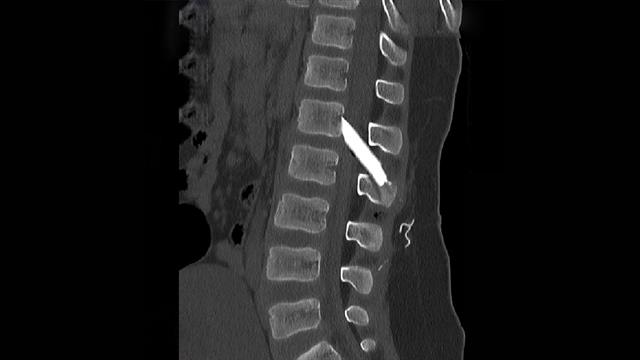

Οι μαγνητικές και αξονικές τομογραφίες πραγματοποιήθηκαν άμεσα, επιβεβαιώνοντας τις αρχικές υποψίες: δύο μεγάλα κομμάτια γυαλιού είχαν ενσφηνωθεί στη σπονδυλική στήλη, εισχωρώντας εντός του σπονδυλικού σωλήνα σχίζοντας την ιππουρίδα και την μήνιγγα που την περιβάλλει.

Ακολούθησε άμεση εισαγωγή του παιδιού στο χειρουργείο, όπου με πολύ προσεκτικούς χειρισμούς και τη χρήση προηγμένου εξοπλισμού, όπως το σύστημα χειρουργικής πλοήγησης, πραγματοποιήθηκε επιτυχής αφαίρεση όλων των κομματιών γυαλιού μετά από ένα πολύωρο και απαιτητικό χειρουργείο.